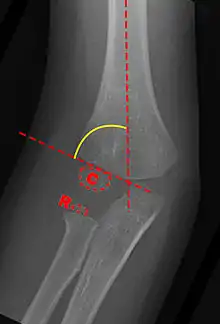

Anterior X-ray

Carrying angle can be evaluated through AP view of the elbow by looking at the Baumann’s angle.[3] There are two definitions of Bowmann's angle:

The first definition of Baumann's angle is an angle between a line parallel to the longitudinal axis of the humeral shaft and a line drawn along the lateral epicondyle.

Another definition of Baumann's angle is also known as the humeral-capitellar angle. It is the angle between the line perpendicular to the long axis of the humerus and the growth plate of the lateral condyle. Reported normal values for Baumann's angle range between 9 and 26°.[7] An angle of more than 10° is regarded as acceptable.[7]